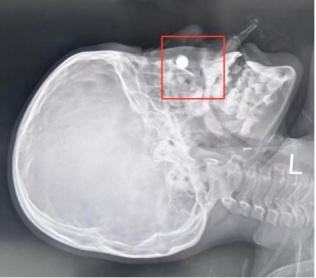

X线平片结果显示,患儿鼻腔深处有一枚高密度圆形异物影。这个发现不仅解释了MRI伪影的来源,也让诊疗思路出现了新的方向。

患儿鼻腔位置有个白色圆形高密度影,提示异物